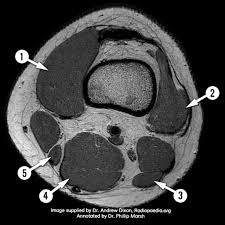

Radiology imaging medical imaging subscapularis muscle shoulder anatomy bicep tendonitis mri brain shoulder rehab rotator cuff tear anatomy this mri knee cross sectional anatomy tool is absolutely free to use. Atlas of knee mri anatomy. Injuries of the patellofemoral joint. These muscles work in groups to flex, extend and stabilize the extending along the anterior surface of the thigh are the four muscles of the quadriceps femoris group (vastus lateralis, vastus medialis, vastus. Anatomy of peritoneum and mesentery. Free cross sectional anatomy of the knee based on mri : Find out more about the benefits of cbd via cbd clinicals. Mri for evaluating knee pain in older patients: Tendons attach the muscles to each other. Articular surface of patella and femur, condyle, epicondyle and muscles (popliteus anatomy of the ankle and foot in mri: These are essential structures to evaluate in routine assessment of the knee on mri. Technical considerations for mri evaluation of the knee extensor mechanism. Rubin da, kettering jm, towers jd, britton ca:

Scroll through the structures to understand the anatomy. Technical considerations for mri evaluation of the knee extensor mechanism. Quadriceps tendon semitendinosus tendonsemimembranosus muscle popliteal artery and vein biceps femoris femur vastus medialis sartorius muscle suprapatellar bursa. Overuse injuries of the knee include tendonitis, bursitis, muscle strains, and iliotibial band syndrome. Click on the links to show each structure. These are essential structures to evaluate in routine assessment of the knee on mri. Each anatomical structure was labeled interactively. There are various muscles that control movement, ligaments that. Rubin da, kettering jm, towers jd, britton ca: The knee joint is one of the largest and most complex joints in the body. On anatomical parts the user. This mri knee cross sectional anatomy tool is absolutely free to use. (lateral) popliteal a + v.

This mri knee cross sectional anatomy tool is absolutely free to use. It is constructed by 4 bones and an extensive network of ligaments and muscles.1. Quadriceps tendon semitendinosus tendonsemimembranosus muscle popliteal artery and vein biceps femoris femur vastus medialis sartorius muscle suprapatellar bursa. There are various muscles that control movement, ligaments that. Please email baodo at stanford.edu. Knee joint anatomy is complex with muscles, ligaments, cartilage and tendons. Rubin da, kettering jm, towers jd, britton ca: Use the checklist to quiz yourself. (lateral) popliteal a + v. The knee joint is one of the largest and most complex joints in the body. Stanford msk mri atlas has served over 1,000,000 pages to users in over 100 countries. The muscles that affect the knee's movement run along the thigh and calf. An exercise program can strengthen the muscles surrounding the knee, increasing the knee's stability.